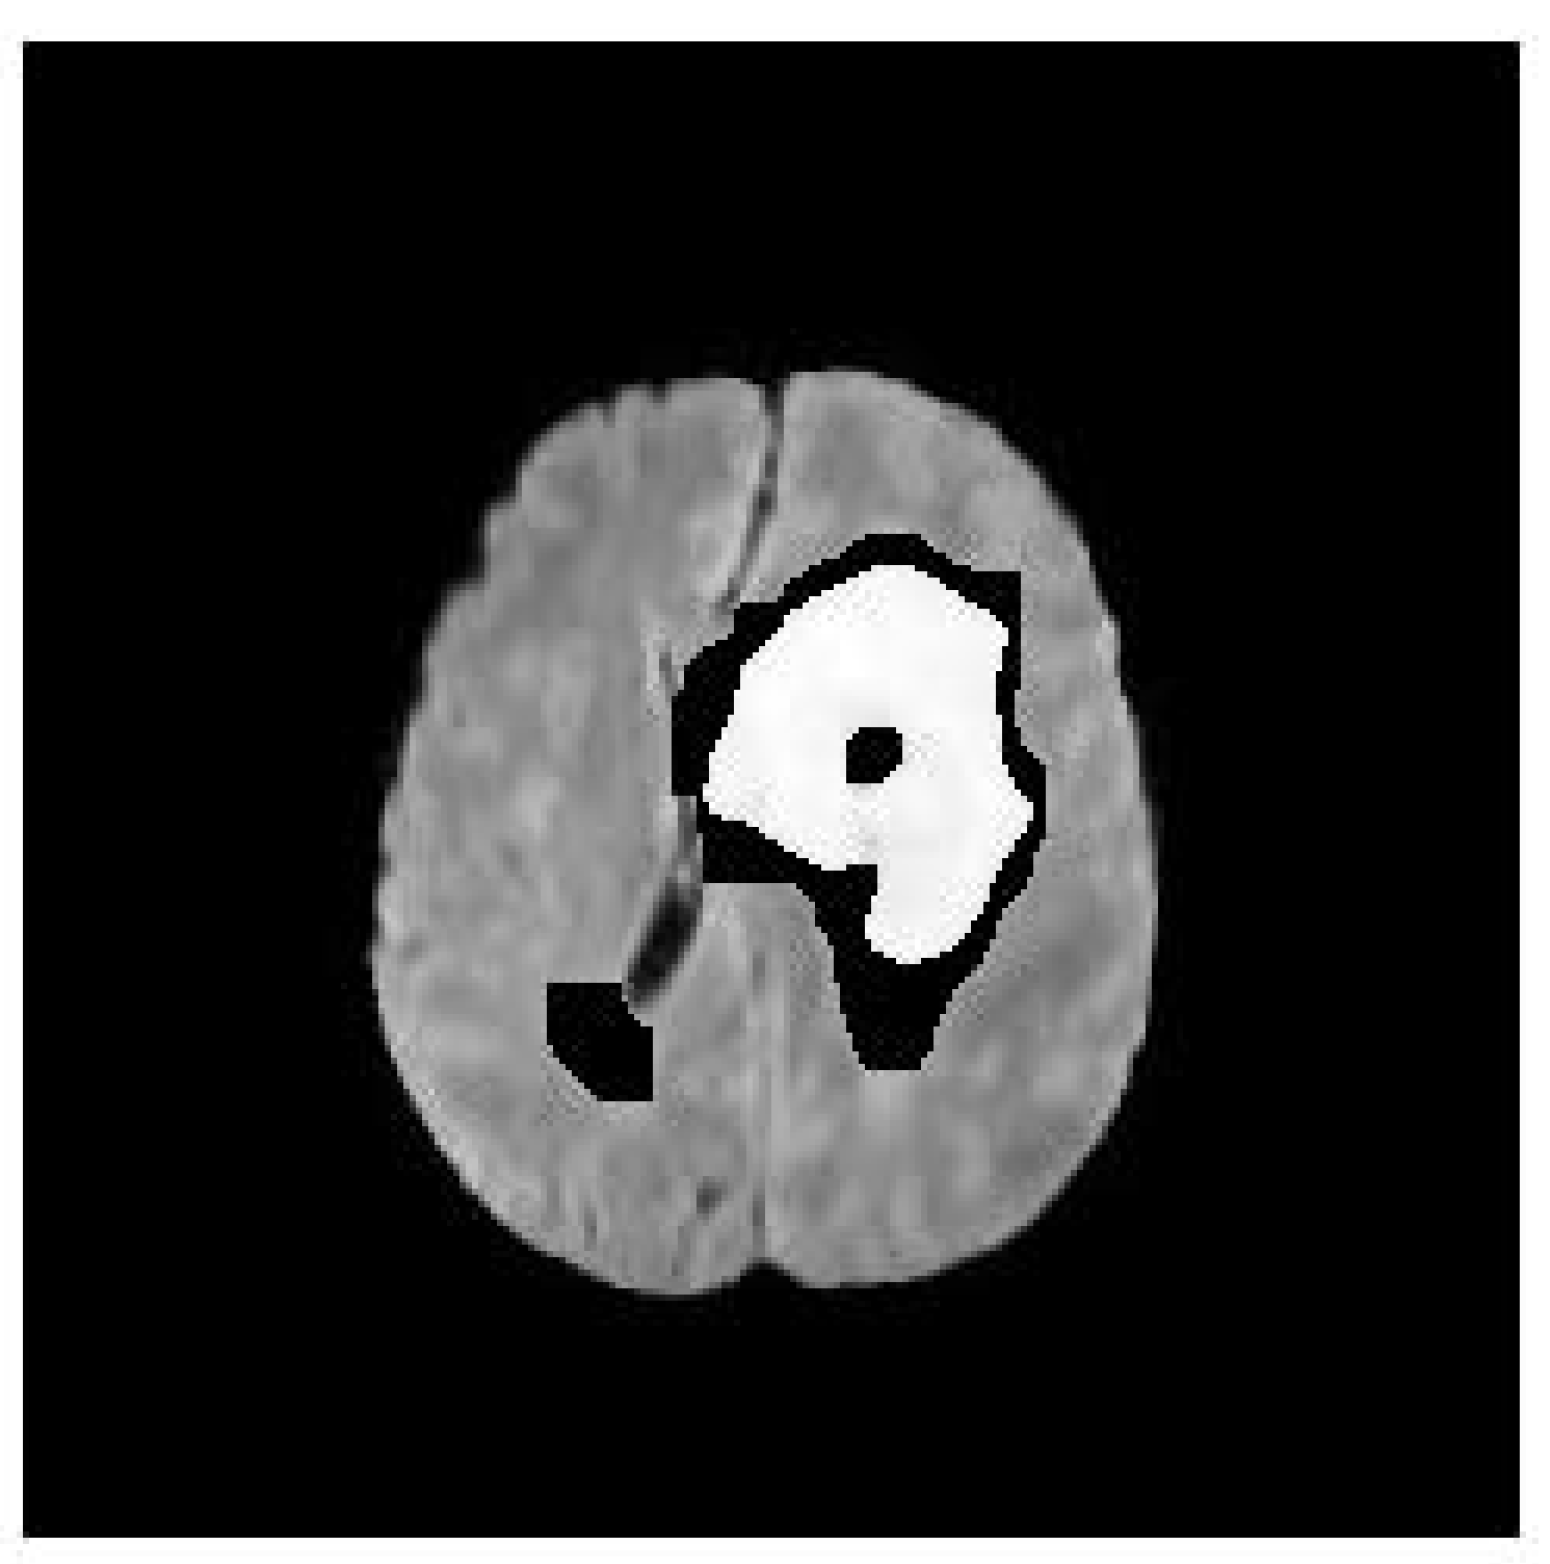

The proposed framework was evaluated on a dataset of brain tumor images. Figure 1 shows the binary mask of the segmented nodule, while Figure 2 presents the color-coded visualization of the segmentation overlaid on the original image. Quantitative metrics, such as area, perimeter, and circularity, were computed for each segmented nodule.

The binary mask in Figure 1 demonstrates the effectiveness of the proposed method in isolating the nodule from the surrounding tissue. The mask is clean and well-defined, with minimal noise, indicating that the combination of anisotropic diffusion and region growing successfully preserves the nodule’s boundaries while reducing artifacts.

Figure 1. Binary mask of the segmented nodule. The mask clearly identifies the nodule region, isolating it from the surrounding tissue. This binary representation is crucial for further quantitative analysis, such as calculating the area and perimeter of the nodule.

Preprints 153268 g001